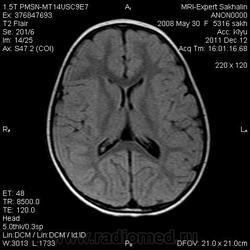

Девочка 3 года.В анамнезе -родовая травма-внутрижелудочковые кровоизлияния 1-2 ст.Задержка психического развития.Со слов мамы, "бывают истерики, хватается ручками за голову, особенно затылочную часть".Как интерпретировать изменения в желудочках, в задних рогах?Ликворную кисту ЗЧЯ отметила.

А вот гипоинтенсивное по Т2 в заднем роге левого бокового желудочка?В других последовательностях нет.

справа киста сосудистого сплетния -она же ксанутрогранулема,пртекаетбессимптомно.в эру доКТ и МРТ диагнстировались только на аутопсии,влевомсплетении -фокус пониженного МРС -возможно обезыствление или гемосидерин  ( ведь было кровоизлияние?)

Здравствуйте! Извините что вклиниваюсь в вашу дискуссию. В дополнение ко всему сказанному мне показалось что для трехлетнего ребенка желудочки несколько великоваты, больше слева. Ликворные пространства не симметричны, опять больше слева. В складочках мозга мелкие, пока, кисточки. Может быть попробовать исключить церебральный арахноидит? Пункцию делали?